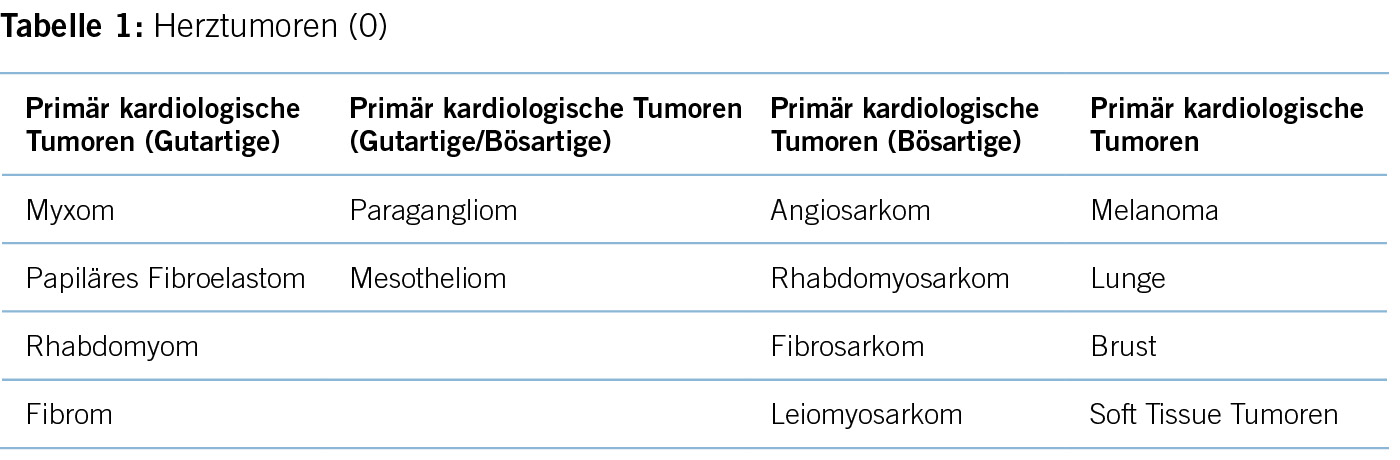

Herztumoren, obwohl im Vergleich zu anderen Herzerkrankungen selten, stellen aufgrund ihrer vielfältigen Ursprünge, variablen klinischen Manifestationen, Komplikationen und komplexen Behandlungsansätzen, einzigartige Herausforderungen dar. Sie können entweder als primäre Tumoren entstehen, die im Herzen selbst ihren Ursprung haben, oder als sekundäre Tumoren, die an anderer Stelle im Körper entstehen und zum Herzen metastasieren (1). Diese Tumoren umfassen eine breite Palette histologischer Typen, einschliesslich gutartiger und bösartiger Neoplasien, von denen jeder seine eigene biologische Verhaltensweise mit entsprechenden klinischen Auswirkungen hat (siehe Tabelle 1) (1).

Von allen primären Herztumoren sind mehr als 75% benigne. Myxome respektive Papilläre Fibroelastome sind zwar die zwei häufigsten primären Herztumore, jedoch beträgt die Häufigkeit der Tumoren nur 0.021%–0.019% (2, 3.)

Im klinischen Alltag gehören die Herztumoren zu einer Rarität. Primäre Herztumore haben eine Prävalenz von weniger als 0.1% (4, 5). Dagegen sind Herzmetastasen deutlich häufiger. Bei mehr als 9.1% der Patienten, die mit einer malignen Krebserkankung sterben, können Herzmetastasen post mortem nachgewiesen werden (5).